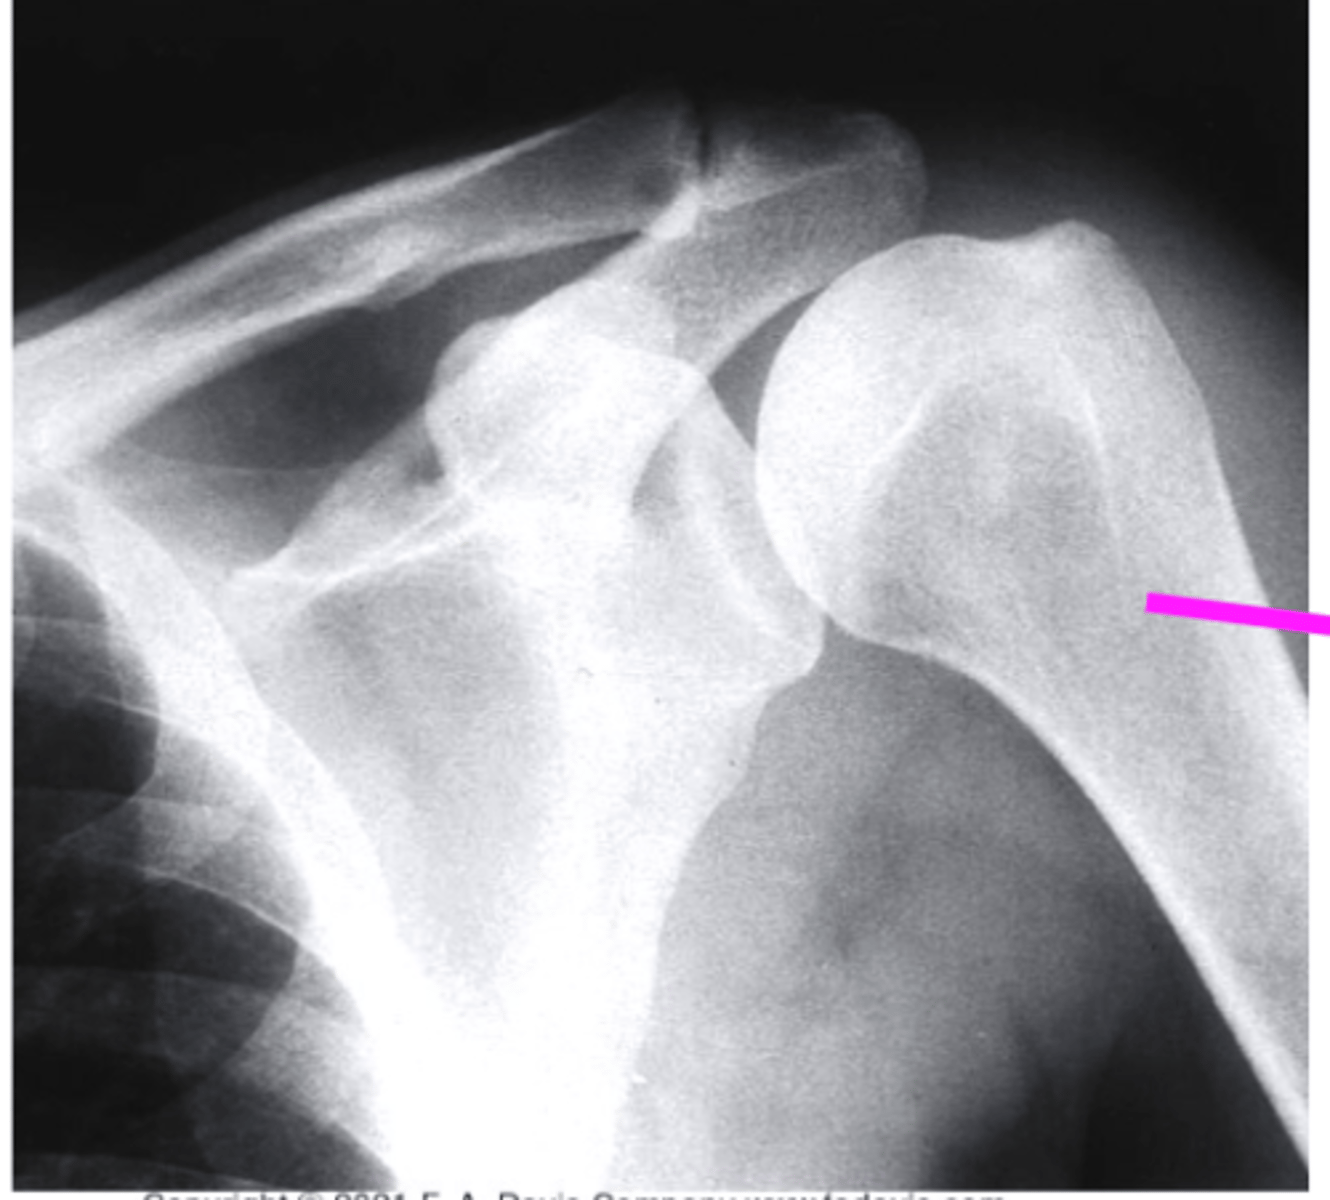

scapular Y lateral

what view is this

clavicle

what does the pink line point to?

coracoid process

acromion of scapula

humeral head

inferior angle of scapula

body of scapula